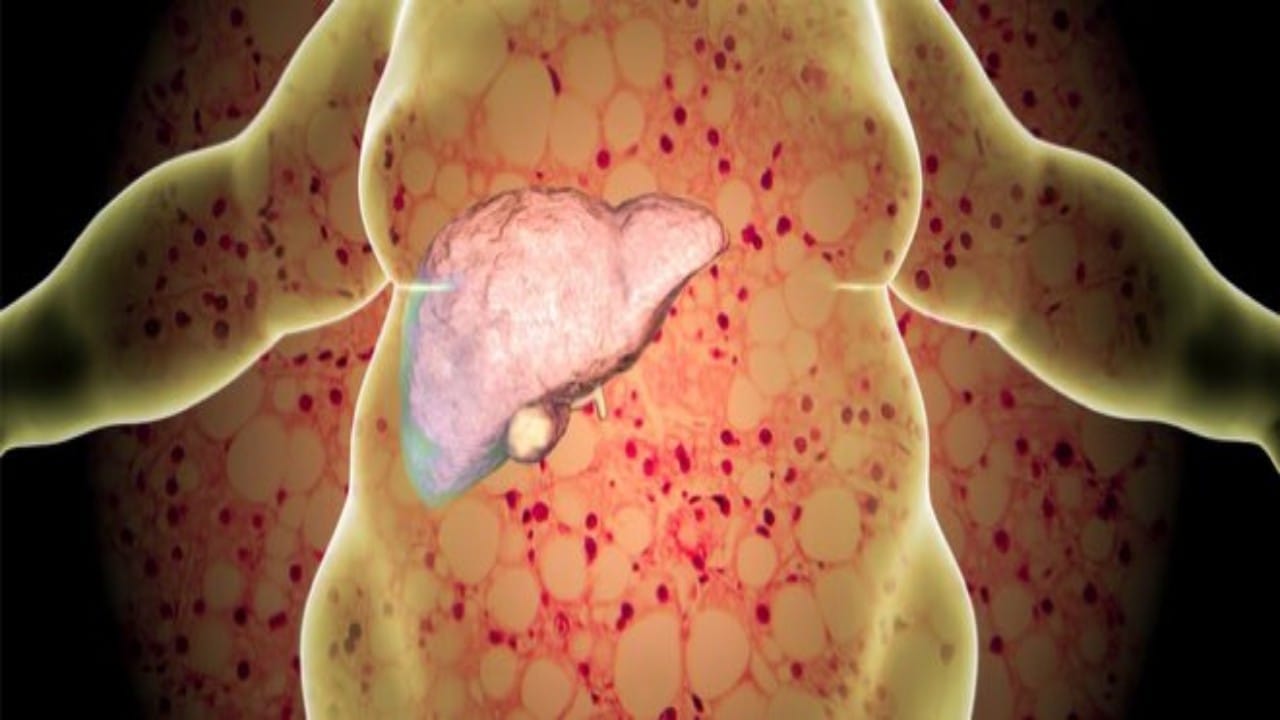

دهون الكبد

الذيابي: دهون الكبد مرض صامت لا يسبب عادةً أعراض

عبدالله الذيابي: الدهون أحد الأسباب الرئيسية لزراعة الكبد